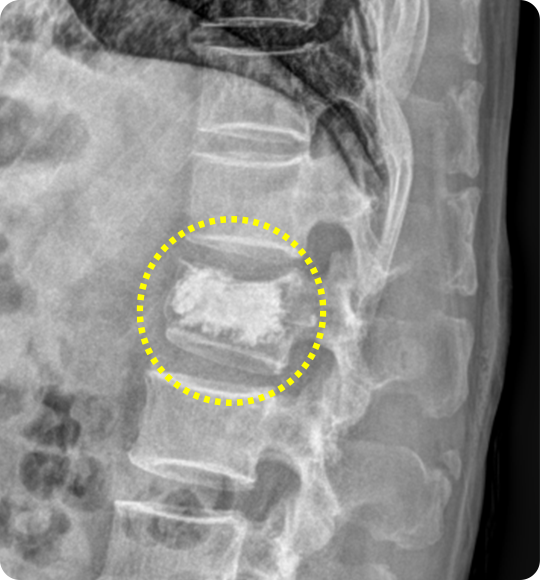

척추체 성형술 전

주저 앉은 모습

척추체 성형술

척추가 골다공증이나 외상으로 압박골절이 발생하면, 골절된 척추체가

주저앉으면서 자세 변화, 만성 통증, 추가 골절로 이어질 위험도 커집니다.

이때 골절로 약해진 척추체 내부에 특수 의료용 시멘트를 주입해 척추를 단단히

보강하고 통증을 완화하는 치료가 바로 척추체 성형술입니다.

척추체 성형술 후